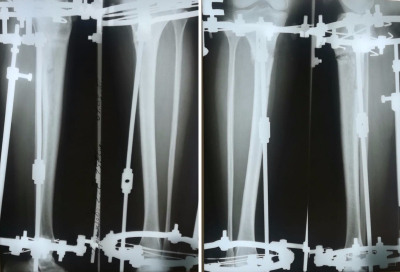

Рентген в 60 дней с момента операции

Дата операции - 04.07.02018г.

Дата снятия аппаратов 04.10.2018г.

Срок сращения 90 дней.